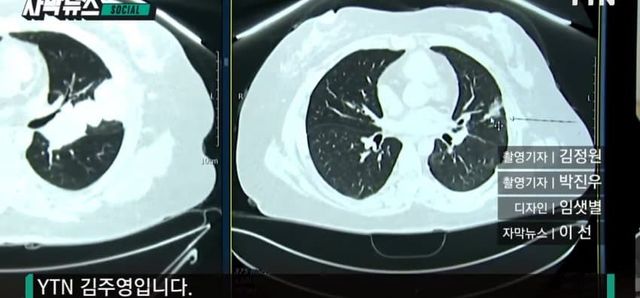

[자막뉴스] 기존 방식으로 어려웠는데…차세대 진단법으로 찾아낸 ‘희귀암’ / YTN

과거 다리 부위에 암이 생겨 치료를 받았던 30대 강 모 씨는 얼마 전 폐로 암이 전이됐다는 청천벽력 같은 진단을 받았습니다살겠다는 의지와 함께 치료에 전념했지만 병세는 전혀 나아질 기미를 보이지 않았고, 최악의 상황까지 다가왔습니다.[강모씨 / NTRK 유전자 변이암 환자 : 저…